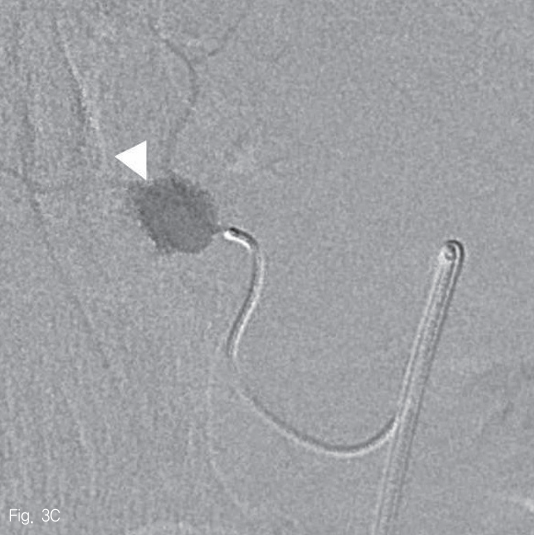

우측 대퇴동맥을 천자하여 5-Fr sheath(Radifocus; Terumo, Tokyo, Japan)를 삽입한 뒤, 5-Fr Cobra catheter(Cook Medical Inc, Bloomington, USA)를 사용하여 상장간막동맥 조영술을 시행하였다. 중간결장동맥의 근위부에 조영제가 채워지는 낭모양의 가성동맥류가 보였다 (Fig. 3A). 중간결장동맥은 상장간막동맥에서 후방으로 기시하여 5-Fr catheter로 선택하기 어려웠다. 0.035-in shapeable guidewire(Radifocus; Terumo, Tokyo, Japan)를 이용하여 중간결장동맥의 근위부까지 5-Fr catheter로 진입하였다 (Fig. 3B). 2.0-Fr microcatheter (Progreat; Terumo, Tokyo, Japan)를 이용해서 병변 직전까지 초선택하였다 (Fig. 3C). N-butyl-2-cyanoacrylate (Histocryl; B. Braun, Tuttlingen, Germany)과 Lipiodol (Guerbet, Paris, France)을 1:2 비율로 섞은 용액(33% glue)으로 색전술을 시행하였고 가성동맥류는 소실되었다 (Fig. 3D). 시술 직후 환자는 통증을 호소하였지만 곧 호전되었다.

Fig 3C

Arteriogram of superior mesenteric artery (SMA) shows a small pseudoaneurysm originating from the middle colic artery (A-C, arrowheads) which has large angle to backward (A). After the superselection of the bleeding branch (C), embolization with 33% glue was performed without any complication (D).